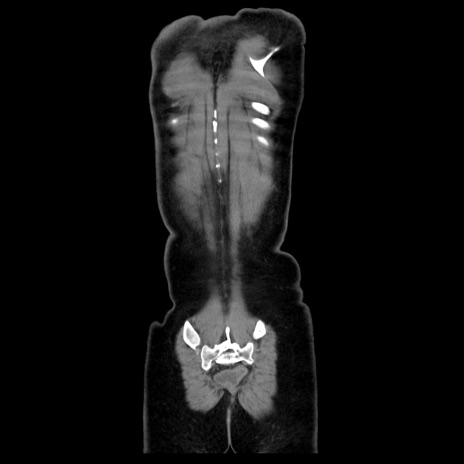

症例39(冠状断像)

【症例】40歳代女性

【主訴】上下腹部痛

【現病歴】2日目から下腹部痛あり。夜間は痛みで眠れなかった。昨日より上腹部痛と下痢が出現。臥位で痛みは軽快したため、休んでいた。本日になって臥位でも立位でも痛みが強くなってきたため救急要請。

【既往歴】子宮内膜症

【身体所見】部:平坦・軟、左上下腹部に圧痛あり、反跳痛あり。

【データ】WBC 21800、CRP 26.78

CT